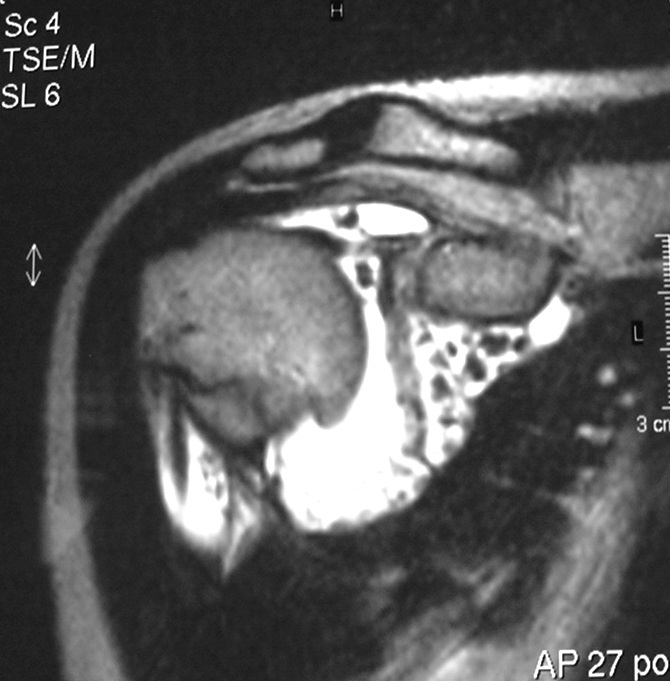

Synovial chondromatosis is an uncommon, benign, process that occurs in large joints, such as the knee (50%), hip, elbow, or shoulder. This process mainly affects synovium and hence most commonly arises from joints and tendons which are lined by synovium. Synovial Chondromatosis may also affect bursae and extend into surrounding soft tissues. This condition is seen in patients between 20 and 50 years of age and most commonly in men (male-female ratio of 2-4/1). The patient usually complains of pain, stiffness, crepitance, swelling, and joint locking. The knee is the most common site to be affected. Symptoms are long-standing and progressive. The plain x-ray may be normal (5 to 33%) or there may be small flecks of calcification (Fig. 1 & 2). On MRI the nodules of cartilage are easily seen. MR imaging may also show synovial thickening, joint erosions and intraarticular calcifications. The signal characteristics of these intraarticular bodies depend of their composition. If mineralization is not present the signal intensity follows the cartilage signal with intermediate signal on T1 images and high signal on T2 weighted MR images. Uniformly calcified bodies follows bone density on all sequences with bone marrow signal centrally and low signal peripherally (Fig. 3-5). Histologically the cartilage is arranged in nodules, which are quite cellular (Fig. 7-9). Synovial lining is present surrounding the cartilage nodules (Fig. 8). The cartilage nodules are often referred to as loose bodies however they are not really loose and embedded in the synovium lining. This is considered a metaplastic condition as opposed to a true neoplastic condition. Rarely it may turn into a malignancy usually a low grade chondrosarcoma. Malignant change is suggested by deep erosions into adjacent bone.

Fig. 4 & 5. MR images of the right shoulder. Axial (Fig. 4) and coronal (Fig. 5) T2-weighted images demonstrate high signal in the right shoulder corresponding with proliferation and swelling of the synovium. Multiple bodies with low signal that follow bone density in all sequences.